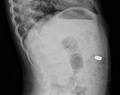

AP X ray showing a 9mm battery in the intestines

Lateral X ray showing a 9mm battery in the intestines